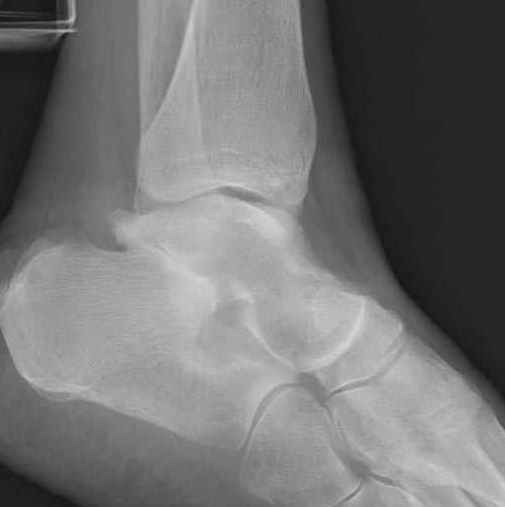

Уважаемые участники русского Ортофорума, поздравляю всех со всеми прошедшими праздниками: Новым годом, Рождеством, Hanukkah, Kwanzaa, желаю участникам всего наилучшего и здоровья.Повреждение таранной кости.Больной 81г автоавария, повреждение таранной кости, здесь снимки. Какие рекомендации?Djoldas Kuldjanov, MDDepartment of Orthopedic SurgerySt. Louis University Medical Center

Вдогонку по поводу перелома таранной кости, больная 81, не страдает диабетом, перелом закрытый, в первый же день поступления ограничились временным наружным фиксатором (как на снимке).

Планировалась открытая фиксация после спадения отека, но больная пожелала лечиться по месту жительству в другом штате..

Примеры на снимке...